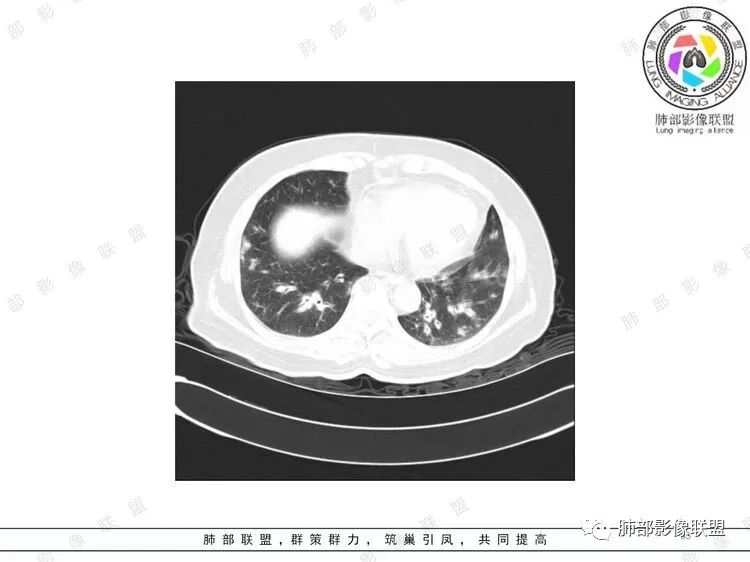

胸CT:双中下肺支气管壁明显增厚,双下肺胸膜下可见实变区。部分病变呈楔形影。

影像上:多发结节沿血管分布;双下叶支气管血管束简直增厚,偏血管,支气管通畅

膀胱炎症

肠系膜血管周围有渗出

左上颌窦粘膜下囊肿,鼻甲肥厚

右肾结石

首先肺部气道来源的病变不符合

因为支气管壁增厚,远端应该小气道病变,这个不是,反而是血管增粗明显

加上结节的分布,支持血管相关病变

累及范围广泛:肠系膜血管?膀胱